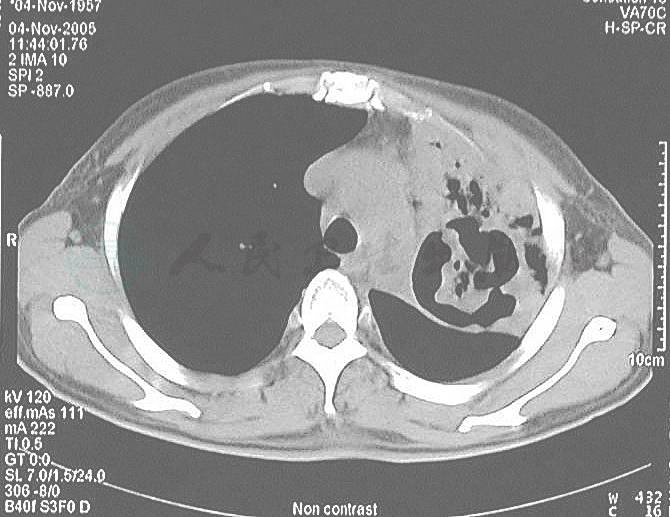

患者,女性,48岁,患2型糖尿病2年,血糖控制不佳。6个月前因糖尿病酮症酸中毒、昏迷入当地医院,予胰岛素等治疗后意识恢复清楚。住院1周时出现发热,体温38℃伴咳嗽,咳痰,查WBC 15×109/L,N 0.80,Hb 120g/L,X线胸片显示左上肺大面积片状渗出影及左侧少量胸腔积液(图1),先后给予左氧氟沙星、克林霉素和头孢哌酮/舒巴坦等抗感染治疗1个月但症状无改善,并出现少量咯血。外院实验室检查:PPD皮试阴性,3次痰查结核菌、真菌培养均阴性,结核抗体阴性,ESR 115mm/1h。曾考虑为肺结核给予异烟肼、利福平、乙胺丁醇治疗1个月,复查胸部CT显示左上肺实变伴空洞形成,洞壁光滑,洞内可见不规则物体(图2),继续抗结核治疗2个月症状仍无改善,并出现大咯血。再次实验室检查显示,WBC 22.7×109/L,N 0.84,Hb 50g/L,X线胸片显示左侧肺野大片高密度阴影(图3),在外院输血、抗结核治疗同时,给予伊曲康唑抗真菌治疗1个月,仍间断出现发热、咯血,并逐渐出现胸闷及双下肢凹陷性水肿,为进一步诊治转入我科。

图2 胸部CT显示左上肺实变伴空洞形成,洞壁光滑但不规则,洞内可见不规则物体(发病2个月)